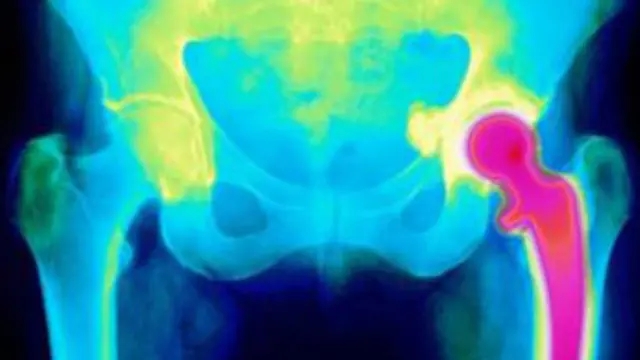

Las regulaciones que rigen en toda Europa sobre estos dispositivos, que incluyen las prótesis de reemplazo de cadera e implantes mamarios, se están actualizando muy lentamente, afirma un informe de expertos del parlamento británico.

El informe fue comisionado después de que se expresaron temores en el Reino Unido sobre la seguridad de las prótesis de cadera.